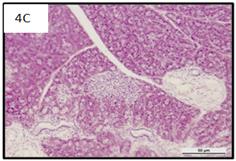

Histological analysis on islet structure revealed a significant difference between both diabetic control Group 2 (fig. 3) and Group 5 (fig. 6A) in comparison to the islets found in Group 1 (fig. 2A). There was no significant difference in the number and shape of islets between the diabetic group (Group 3) in fig. 4A-C and Group 1. Conversely, diabetic Group 3A (fig. 5A) showed less number of islets than that of diabetic islets in Group 3.

We observed that the control untreated rats (Group 1) showed the normal pancreatic islet structure (fig. 2A). In contrast, pancreatic sections of alloxan induced diabetic rats (Group 2) revealed islets that were comparatively smaller in size and have a shrunken appearance, exhibiting how islet cells have degenerated (hydropic degeneration) and necrotised (fig. 3A). 10 w of VCO treatment on diabetic rats (Group 3) revealed that some sections have regenerated islet cells (fig. 5A) despite these animals remaining hyperglycaemic (Group 3A) at the end of the study. Pancreatic sections of previously diabetic recovered animals that have recovered from hyperglycaemia (Group 3) indicated that the islet morphology was near normal in appearance with round nuclei and abundant cytoplasm (fig. 4A-C) and are similar in comparison to the islets from animals in the control group (fig. 2A). Nevertheless, light hydropic degeneration and necrosis was evident in the islet cells of diabetic Group 3A (fig 5A), however the damage towards the islets was not as severe as those found in control Alloxan only group (fig. 3A), only exhibiting a slightly vacuolated cytoplasm. 8 w of VCO treatment prior to ablation by alloxan failed to show any protective effects against substantial islet damage, however, we note that the extent of severity of islet damage was less compared to that of the alloxan only control group (fig. 3A).

Fig. 4: Microscopic features of alloxan induced diabetic rat with 10 w of VCO treatment and recovering from hyperglycaemia